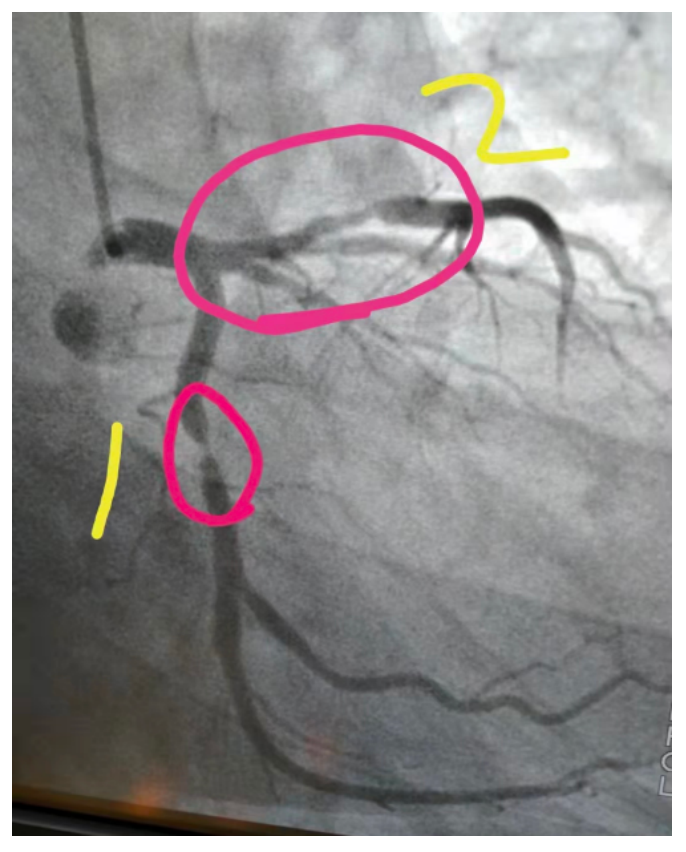

这是一位男性42岁患者,1年前反复胸痛,最后确诊为冠心病,心绞痛。随后做了心脏造影,图中标出的1号血管,当时重度狭窄98%以上,马上就要堵塞了。这种严重的血管狭窄,就是有斑块引起的,单纯通过吃药,包括阿司匹林、他汀、洛尔、单硝酸等等药物,都无法控制心绞痛。所以这种严重的狭窄,不得不通过支架解决。植入支架后血管管腔恢复正常,血流恢复正常,心绞痛症状得到控制。

标为2号的血管,也有一定的斑块,属于中度狭窄,暂时不用支架。但如果这种中度狭窄不正规控制,那么斑块会加重,甚至引起重度狭窄,到时候还可能继续放支架。

1年多过去了,患者来复查了,1号血管,原来的支架内通畅,没有出现任何再狭窄的情况;2号血管,原来的斑块缩小了,几近消失了。